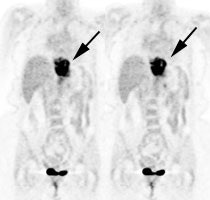

Metastatic esophageal carcinoma: The patient presented for evaluation of a pulmonary nodule. PET revealed tracer uptake in the nodule (black arrow), as well as in an esophageal mass (red arrow), para-esophageal adenopathy, and liver metastases (blue arrows). |